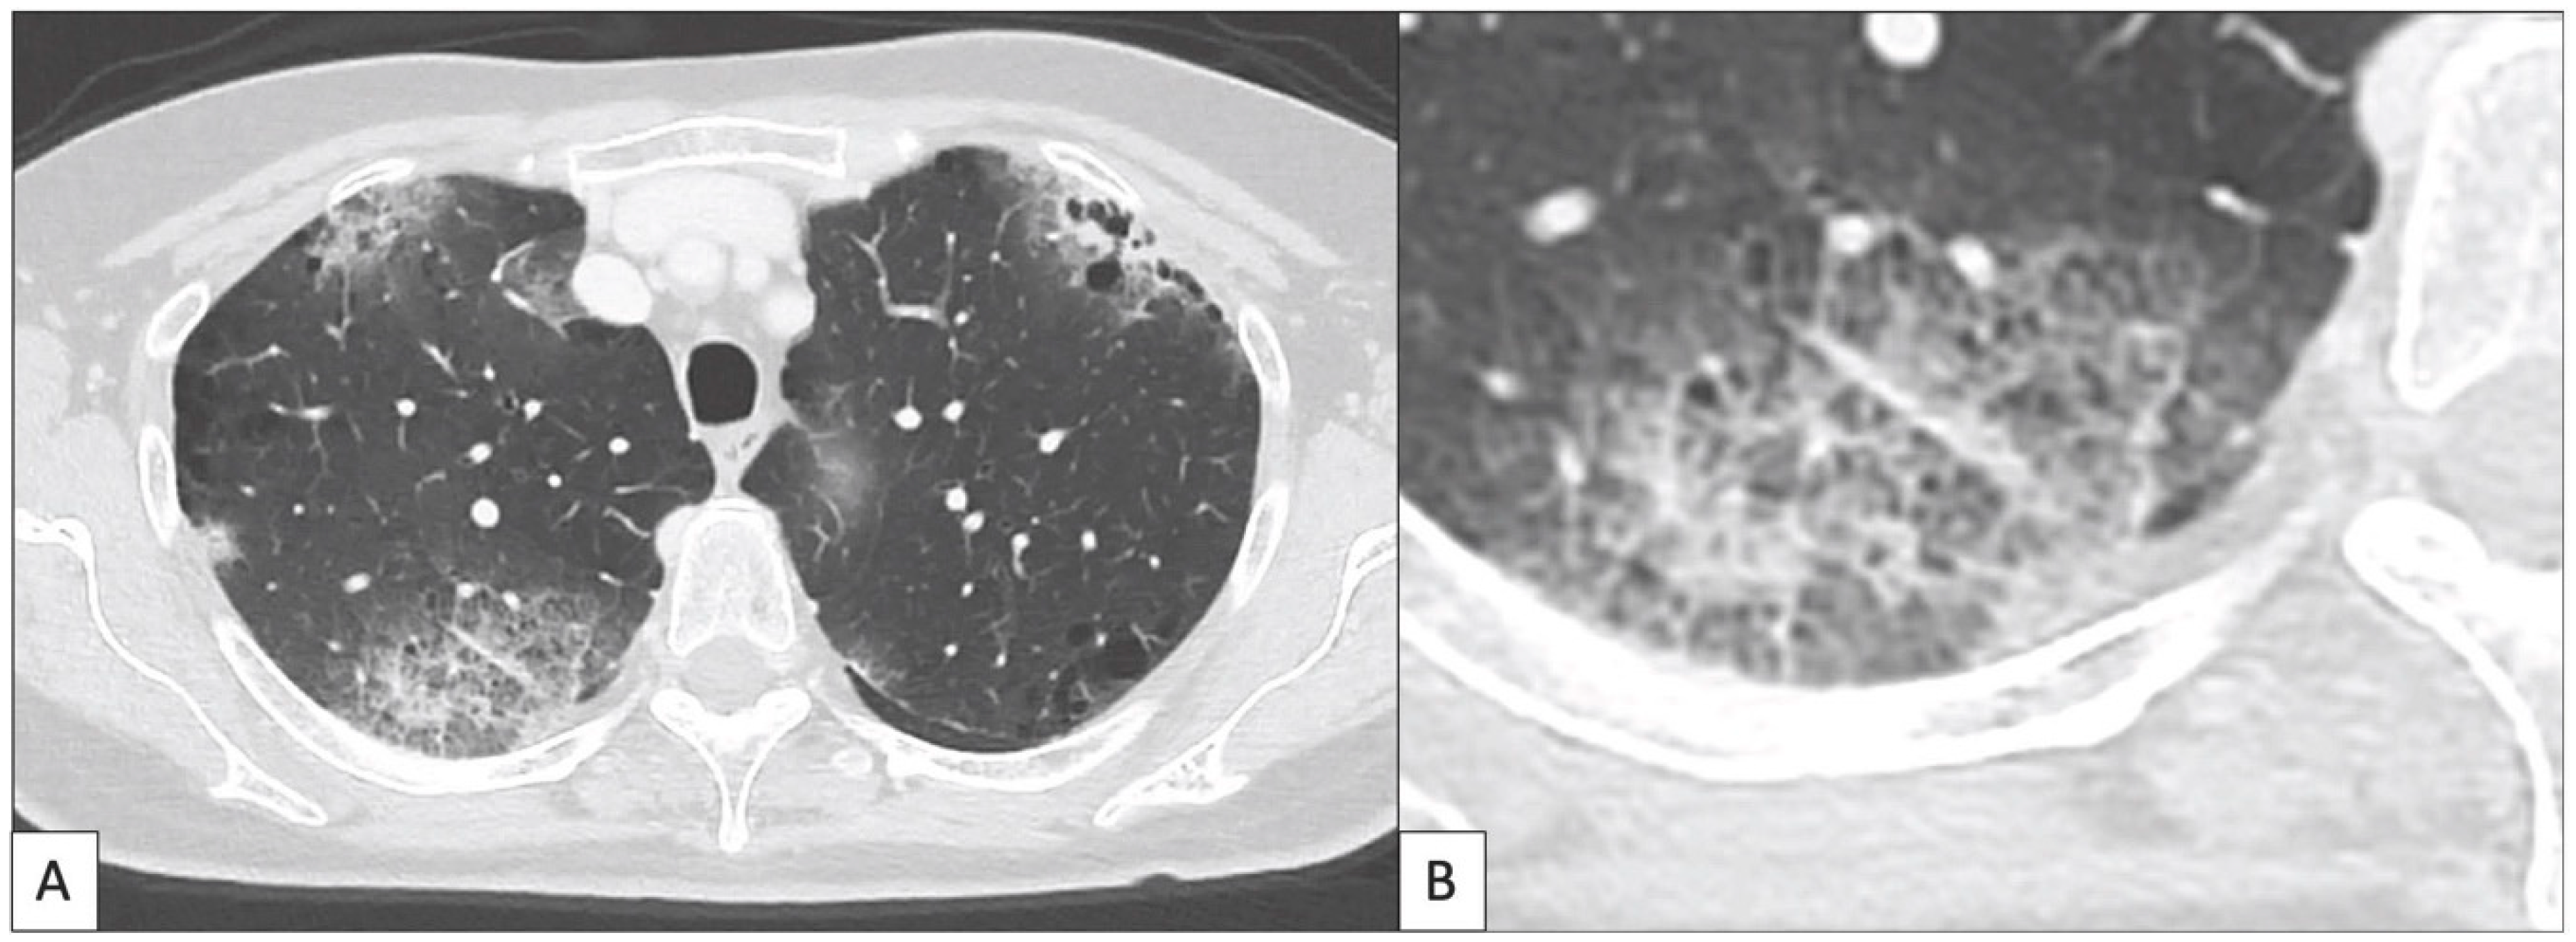

- Nishino, M.; Ramaiya, N.H.; Awad, M.M.; Sholl, L.M.; Maattala, J.A.; Taibi, M.; Hatabu, H.; Ott, P.A.; Armand, P.F.; Hodi, F.S. PD-1 Inhibitor-Related Pneumonitis in Advanced Cancer Patients: Radiographic Patterns and Clinical Course. Clin. Cancer Res. 2016, 22, 6051–6060. [Google Scholar] [CrossRef] [PubMed]